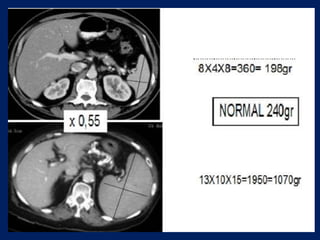

This document discusses imaging of the spleen and summarizes various congenital anomalies and pathologies that can affect the spleen. Some common congenital anomalies mentioned include accessory spleens, asplenia, polysplenia, and splenic fusions. Acquired conditions like repeated infarctions, infiltration, tumors, and cysts can also cause splenomegaly or functional asplenia. Wandering spleen is discussed as a rare congenital anomaly where the spleen lacks attachments and is mobile within the abdomen. Various grades of splenic lacerations and examples of splenic imaging findings are also briefly summarized.